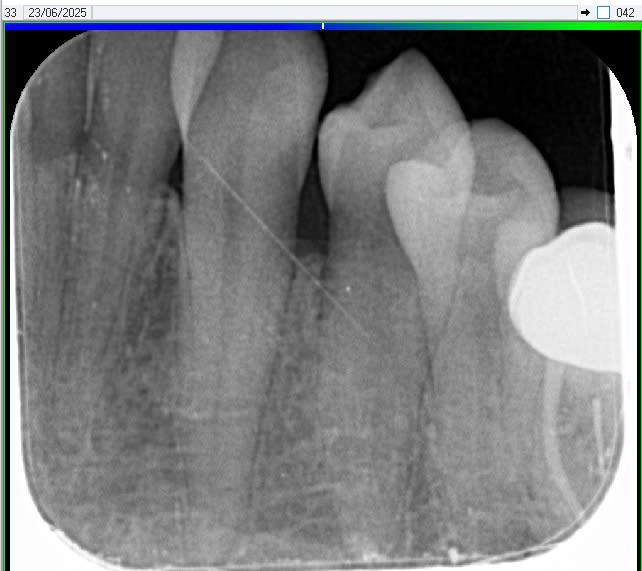

Apres avoir passé 10 jours à bien passer la brossette interdentaire avec de l'eau oxygénée et du bicarbonate, la patiente sans antécédent médical présente toujours une inflammation de la papille entre 33 et 34.

Un diasteme est présent.

A la radiographie, je suspecte une lésion : je lèverai bien un lambeau et vous?

Y a pas une carie en distal de la 33 ?

Pas visible en bouche, je sens rien à la sonde.

Elle serait sous gingivale... c'est ce que je devine à la RVG qui n'est pas terrible.

Pas impossible cela dit mais la petite image à la radio me fait personnellement plus penser à une simple carie ou artefact.